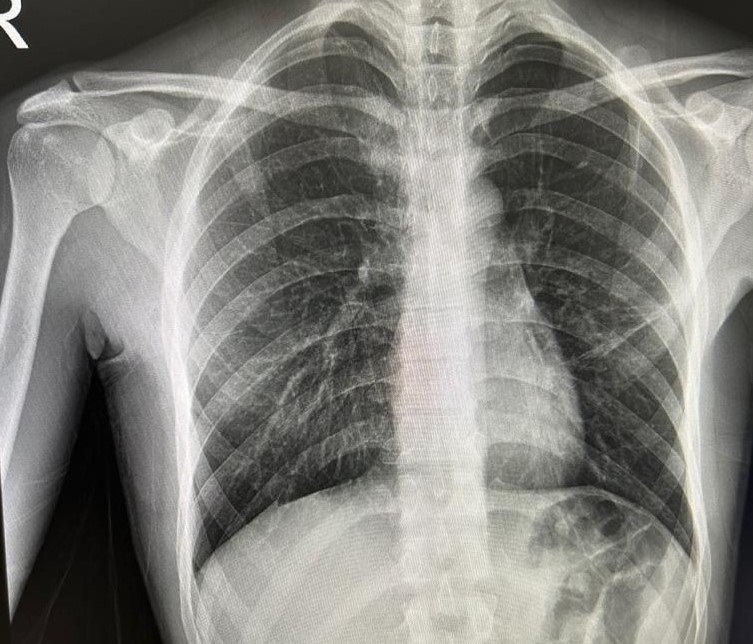

Bayburt'ta nefes darlığı şikayetiyle acil servise başvuran ve daha önce de spontan pnömotoraks (akciğer sönmesi) öyküsü bulunan bir hasta, Göğüs Cerrahisi Uzmanı Op. Dr. Halil Kolcu tarafından yapılan başarılı müdahaleyle sağlığına kavuştu.

Yeniden akciğer sönmesi tanısı konulan hastaya, Op. Dr. Halil Kolcu tarafından 3 santimetrelik tek kesiyle kapalı olarak cerrahi tedavi uygulandı. Bilinci açık ve uyanık bir şekilde işlem uygulanan hasta, başarılı geçen operasyonun ardından aynı gün içerisinde taburcu edildi. Yapılan cerrahi müdahale ile hastanın sağlığına kavuştuğu öğrenildi.